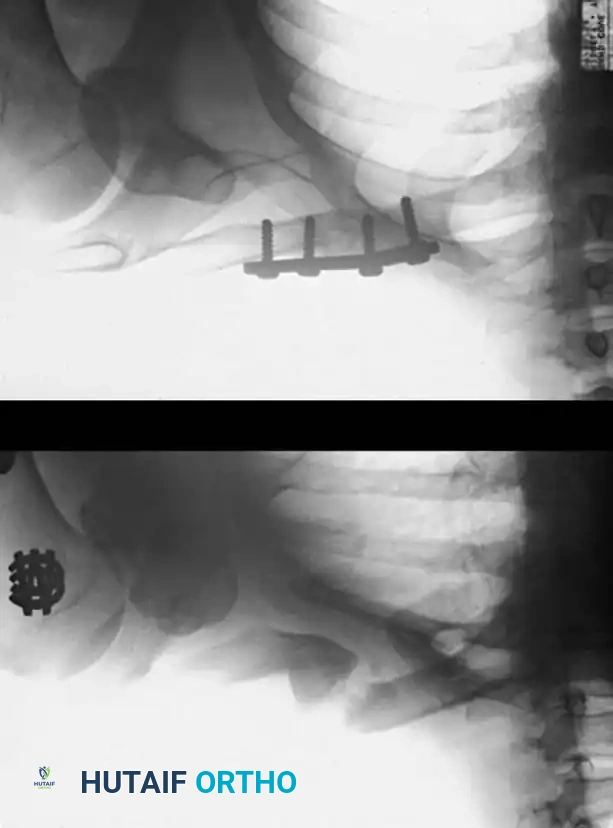

* Fixation: Rigid internal fixation using low-profile mini-fragment plates (2.0 mm or 2.4 mm systems) is the gold standard. If a segmental defect is created after debridement, structural autograft (e.g., iliac crest) is required to maintain metatarsal length and prevent transfer metatarsalgia.